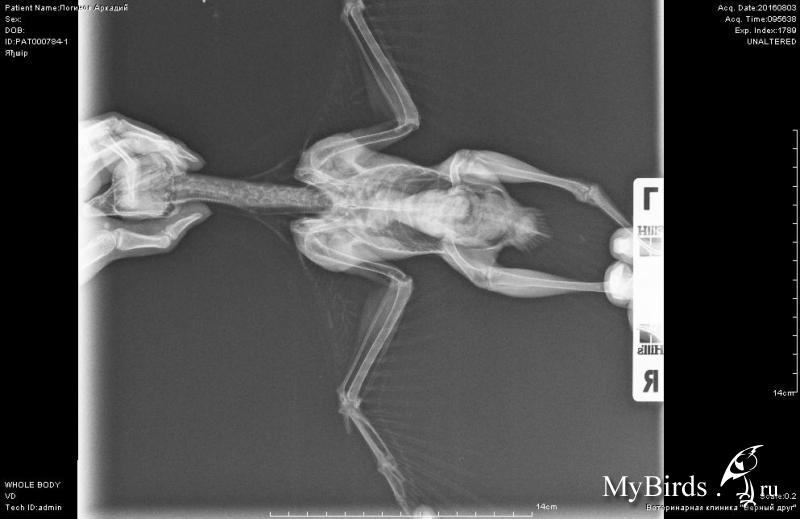

Сегодня сделали рентген и копрограмму (фото).

Помёт у него плохой, кал зеленовато-коричневый, жидкий. Причём какает он прям очень часто, чаще, чем другой воронёнок. В целом подвижный, бойкий, кусается. Как го лечить и вообще, отчего такой плохой помёт?

olinca, стукнитесь к Александру в личку, http://www.mybirds.ru/forums/index.php?showuser=26623, чтобы рентген посмотрел и результат анализа.